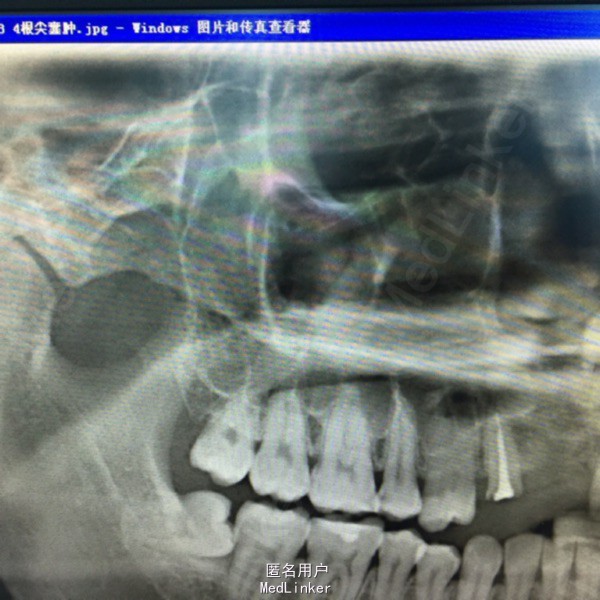

上前牙烤瓷冠修复,13牙冠缺损,叩(+),行桩冠修复。曲面断层片示:13、14根尖可见4x2cm阴影,边缘可见白色阻射线。

诊断:13、14根尖囊肿 处理:1、拆除桩冠。 2、13行牙髓治疗。 3、囊肿行开窗引流术。

患者每天以生理盐水冲洗,2一4次/天,半年复查X片。 该患者1年半后,可见囊腔缩小,新骨长入。无需行囊肿挖除术。